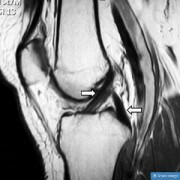

PCL損傷の治療は、手術をしなくても成功する

ACL(前十字靭帯)損傷よりは頻度は少ないものの、PCL(後十字靭帯)の損傷も起こる可能性はあり、適切な処置をしなければ深刻な膝の問題を引き起こします。PCL損傷は、膝からの転倒、交通事故、スポーツ障害などのよくあるメカニズムで起こりえます。場合によっては靭帯の再建手術が推奨されますが、長期的にみて、ACL損傷の手術の結果よりうまくいかない傾向にあるようです。